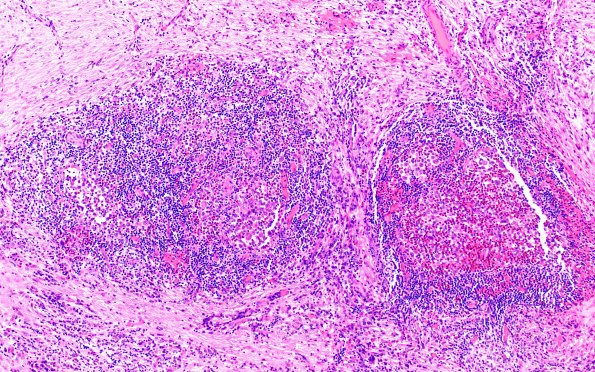

Washington University Experience | NEOPLASMS (HEMATOLYMPHOID) | Langerhans Cell Histiocytosis (LCH) | 24B3 LCH (Case 24 H&E 10X 1B

24B3-7 The infiltrate includes scattered lymphoid aggregates, numerous eosinophils forming clusters and microabscesses, and aggregates of histiocytic cells with prominent nuclear grooves and nucleoli in a subset. (H&E)